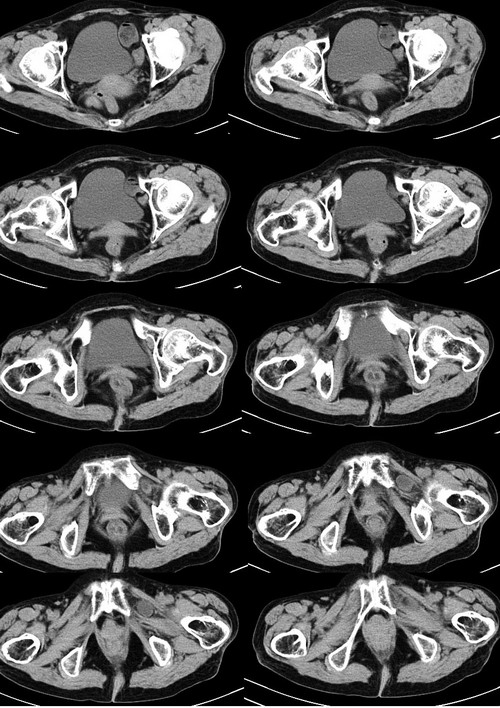

患者女性75岁,腹痛9h余,左腹股沟区可触及一包块,境界不清,压之疼痛明显。

左侧腹股沟股疝。

疝囊经股环,股管向股部卵圆窝突出的疝称为股疝。多见于中年以上妇女。这是因为女性骨盆较宽广,联合肌腱和腔隙韧带较薄弱,以致股管上口宽大松弛的缘故。